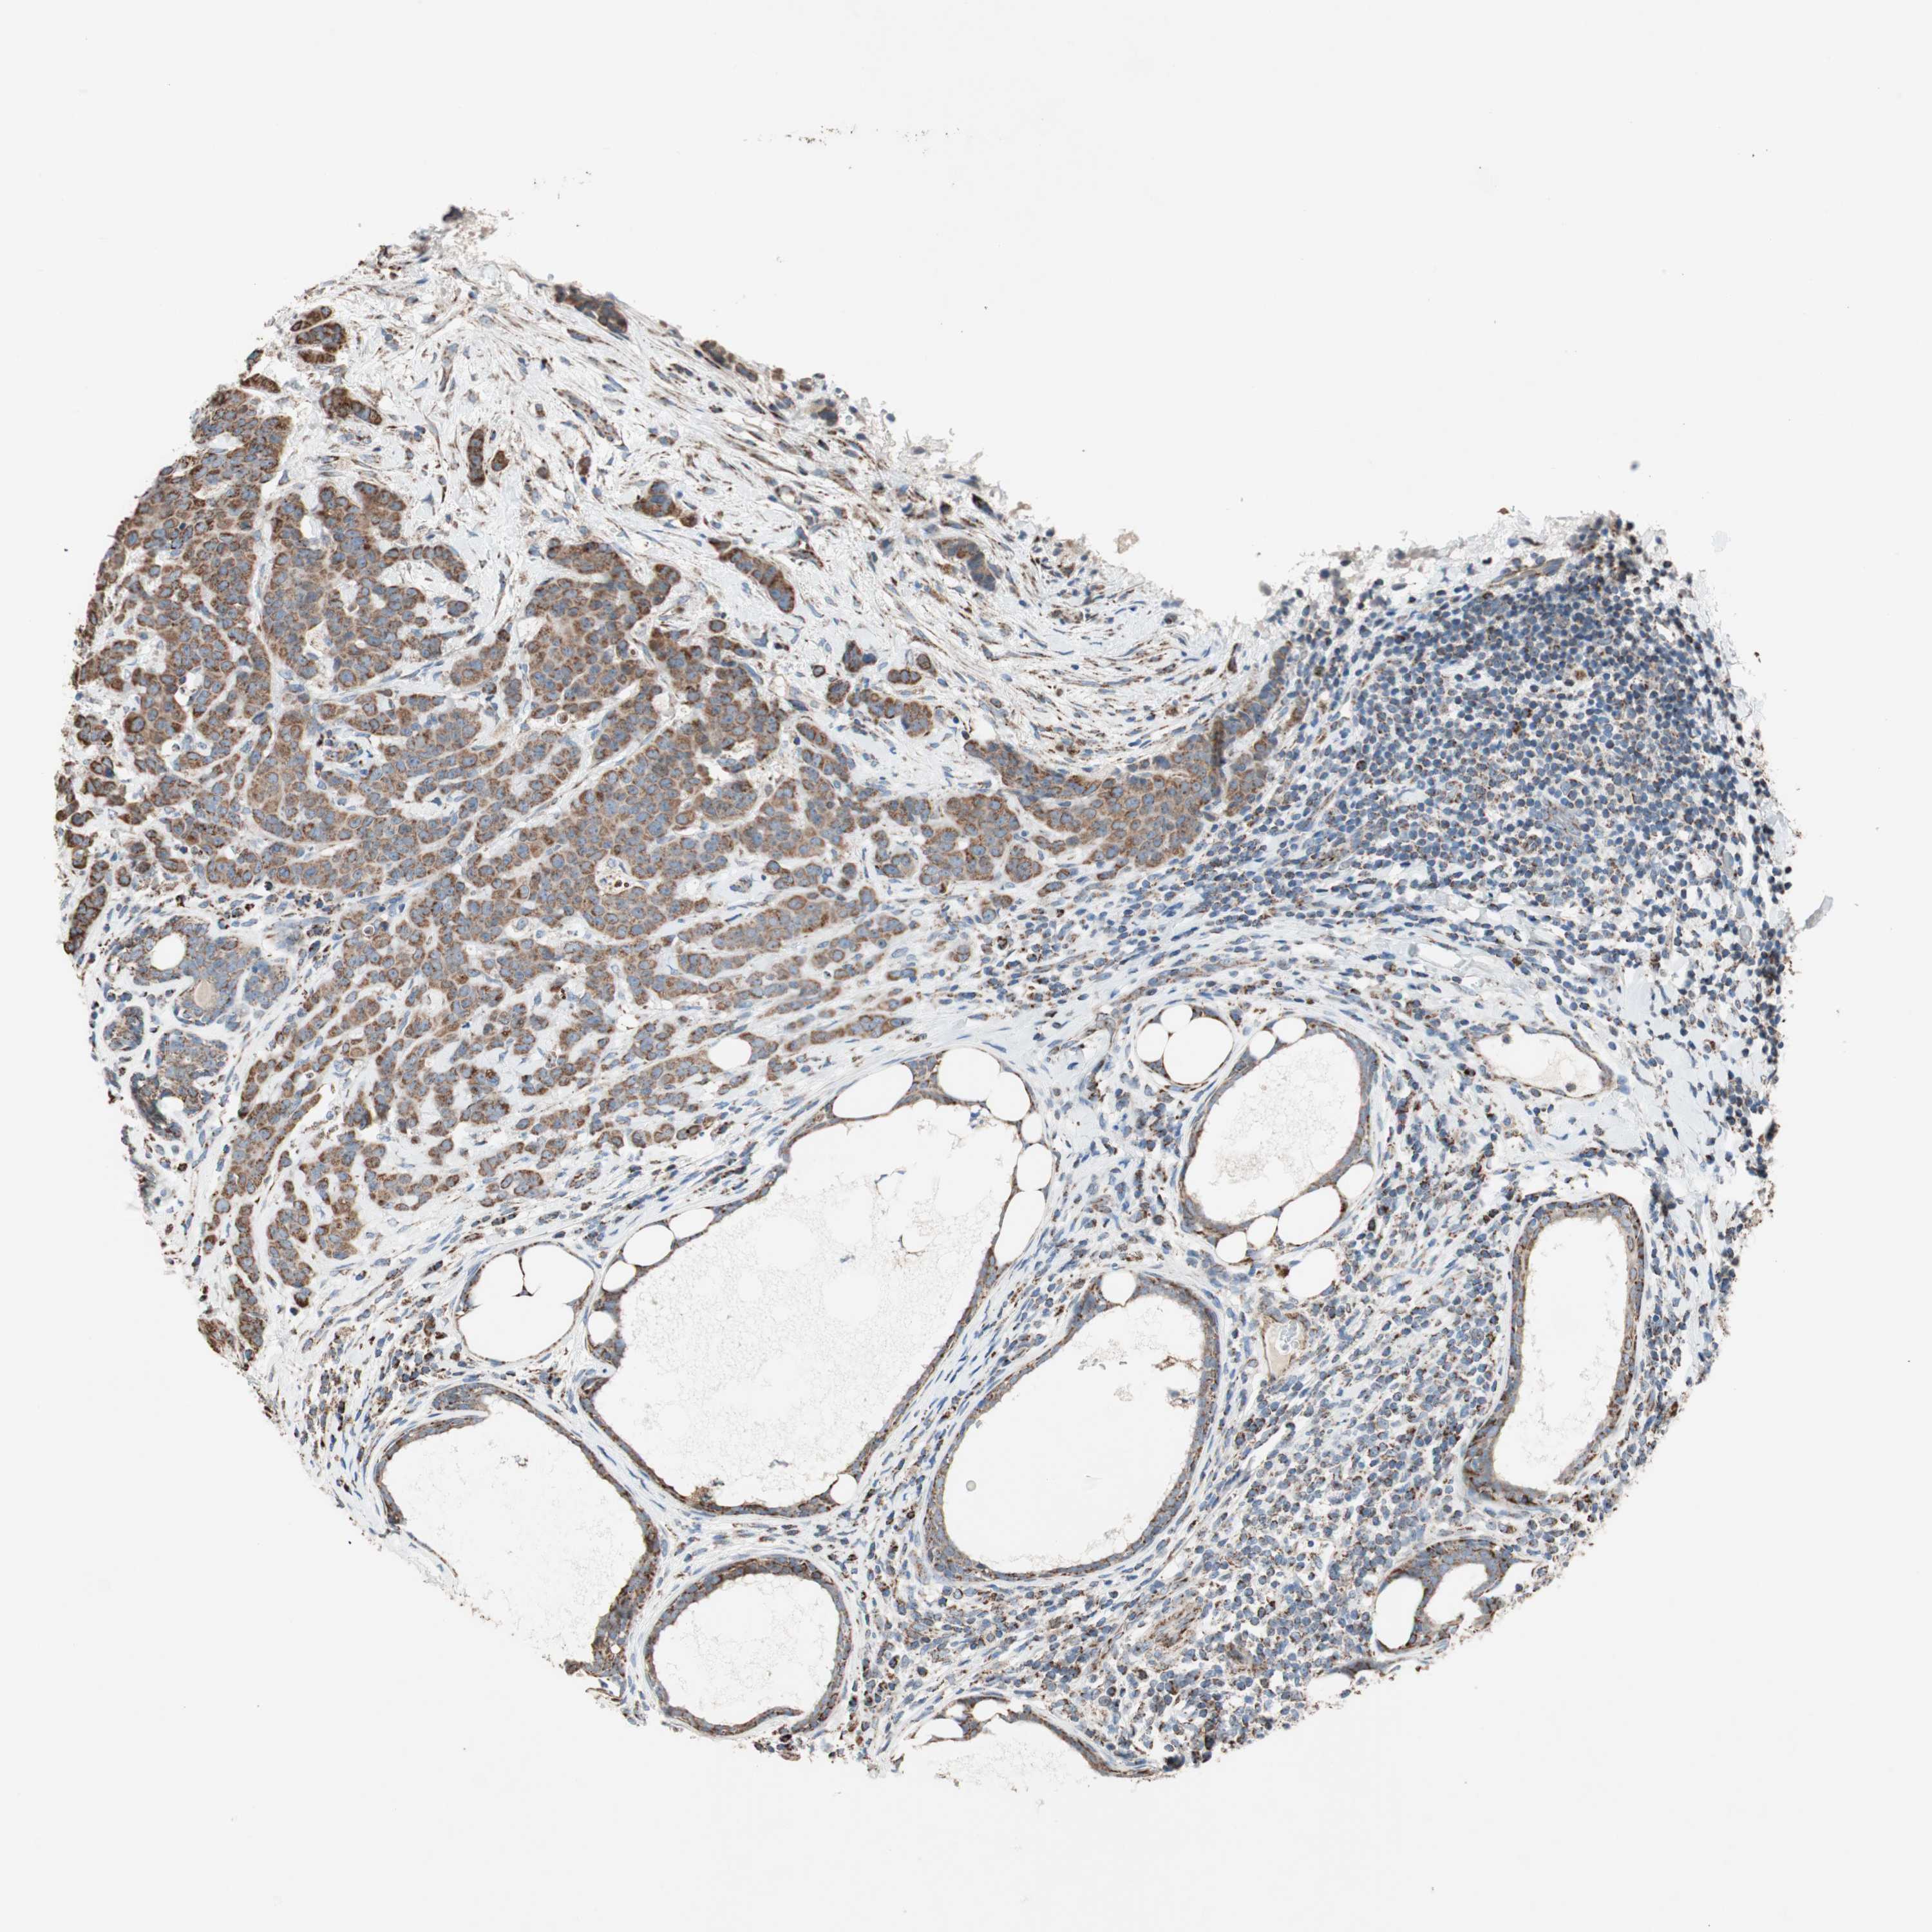

CANCER BREAST CANCER Show tissue menu

BRCA TCGA BRCA VALIDATION PROTEIN EXPRESSION

ANTIBODIES

AND

VALIDATION